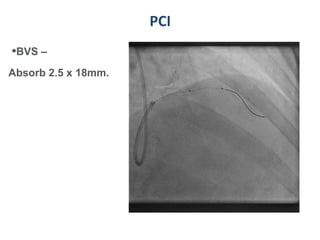

PCI

•BVS –

Absorb 2.5 x 18mm.

Scaffold deployed

● Absorb – BVS

deployed at

nominal press. of

7 atm – 30sec with

incremental

pressure of 2 atm

at 5 sec interval.